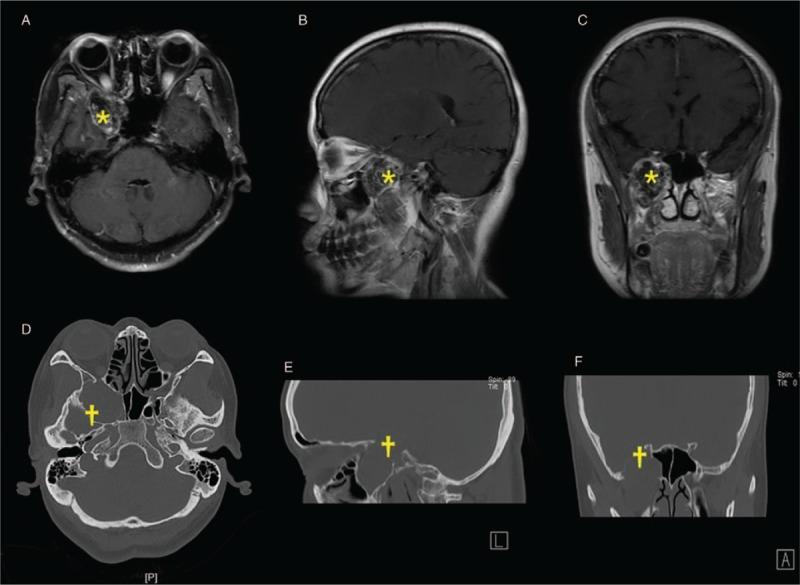

The endoscopic transnasal approach has been proven to have advantages on the removal of the tumors in pterygopalatine fossa (PPF) and infratemporal fossa (ITF). Herein, this study aimed to describe a modified approach for resection of the tumors in these areas, both in cadaveric specimen and clinical patients.

METHODS

The 20 adult cadaveric specimens and five patients with tumors in PPF and ITF were enrolled in this study. For the cadaveric specimens, ten were simulated anterior transmaxillary approach and ten were performed modified endoscopic transnasal transmaxillary approach. The exposure areas were compared between two groups and main anatomic structure were measured. Surgery was operated in the five patients with tumors of PPF and ITF to verify the experience from the anatomy. Perioperative management, intraoperative findings and postoperative complications were recorded and analyzed.

RESULTS

The modified endoscopic transnasal transmaxillary approach provided as enough surgical exposure and high operability to the PPF and ITF as the anterior transmaxillary approach did. The diameter of maxillary artery in the PPF was 3.77 ± 0.78 mm (range: 2.06-4.82 mm), the diameter of middle meningeal artery in the ITF was 2.79 ± 0.61 mm (range: 1.54-3.78 mm). Four patients who suffered schwannoma got total removal and one of adenocystic carcinoma got subtotal removal. The main complications were facial numbness and pericoronitis of the wisdom tooth. No permanent complication was found.

CONCLUSIONS

With the widespread use of neuroendoscopy, the modified endoscopic transnasal transmaxillary approach is feasible and effective for the resection of tumors located in PPF and ITF, which has significant advantages on less trauma and complications to the patients.

经鼻内镜入路已被证明在切除翼腭窝(PPF)和颞下窝(ITF)肿瘤方面具有优势。在此,本研究旨在描述一种改良的方法,用于切除这些区域的肿瘤,包括在尸体标本和临床患者中。

方法

本研究纳入了 20 具成人尸体标本和 5 例 PPF 和 ITF 肿瘤患者。对于尸体标本,10 例模拟经前上颌窦入路,10 例采用改良经鼻内镜经上颌窦入路。比较两组暴露面积,测量主要解剖结构。对 5 例 PPF 和 ITF 肿瘤患者进行手术,验证解剖学经验。记录和分析围手术期管理、术中发现和术后并发症。

结果

改良经鼻内镜经上颌窦入路为 PPF 和 ITF 提供了与经前上颌窦入路相同的足够手术暴露和高操作性。PPF 中上颌动脉直径为 3.77±0.78mm(范围:2.06-4.82mm),ITF 中脑膜中动脉直径为 2.79±0.61mm(范围:1.54-3.78mm)。4 例神经鞘瘤患者均获得全切,1 例腺泡状腺癌患者获得次全切。主要并发症为面部麻木和智齿冠周炎。无永久性并发症。

结论

随着神经内镜的广泛应用,改良经鼻内镜经上颌窦入路对于切除 PPF 和 ITF 部位的肿瘤是可行和有效的,与传统方法相比,对患者的创伤和并发症更小。